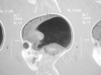

Varón de 6 meses que ingresa por neumonía por Haemophilus influenzae. Tras una mejoría inicial con tratamiento antibiótico progresa hasta insuficiencia respiratoria grave hipercápnica no hipoxémica con alta demanda ventilatoria que requirió intubación. Antecedentes familiares: hermana de 9 años portadora de válvula ventrículo peritoneal por hidrocefalia congénita, colpocefalia, agenesia parcial cuerpo calloso, quiste aracnoideo e hipoacusia neurosensorial bilateral. Antecedentes personales: embarazo controlado por hidrocefalia. Cesárea a las 37 + 6 semanas. Apgar 9/10. Peso: 2.550 g (P25), PC: 37,5 cm (> P90). Ecografía trasfontanelar y resonancia magnética (RM): colpocefalia con agenesia cuerpo calloso, dilatación sistema ventricular a expensas de astas occipitales y ambos ventrículos laterales sin dilatación del III ventrículo. No requirió derivación ventriculoperitoneal de líquido cefalorraquídeo. Ingreso a los 2 meses por bronquiolitis virus respiratorio sincitial negativo.

A su ingreso en la unidad de cuidados intensivos, conectado a ventilación mecánica, presenta abundante producción de esputo purulento, fiebre y leucocitosis. Radiografía de tórax: infiltrados alveolares sin condensación lobular. Tras permanecer 48 h la asistencia respiratoria, se extuba, presentando una ventilación adecuada con un índice de oxigenación de 250 y un nivel de reactividad normal. A los 2 días comienza con retención progresiva de CO2 sin estridor ni signos de trabajo respiratorio, precisando reintubación nasotraqueal. Después de 3 días se encuentra consciente y orientado con hipotonía generalizada, arreflexia, ausencia de sostén cefálico y sedestación. Respuesta patológica ante suspensión vertical y horizontal con atonía de miembros y bamboleo de cabeza, actitud "en libro abierto" con extensión pasiva de tobillos. Su situación clínica es estable con un trabajo respiratorio aparentemente fisiológico y un intercambio gaseoso normal por lo que a los 3 días se extuba por segunda vez. Aparece de nuevo hipercapnia con fracaso de respiración espontánea requiriendo reintubación. Con el diagnóstico de insuficiencia respiratoria restrictiva de origen neuromuscular secundaria a cuadro de hipotonía generalizada se realiza test del tensilón (normal) y potenciales evocados estoacústicos (hipoacusia bilateral perceptiva grave, potenciales visuales normales). Tomografía computarizada craneal y RM: colpocefalia importante (fig. 1). Cifras de creatincinasa (CK) normales. Electromiograma: patrón miopático de características no inflamatorias de distribución generalizada aunque afecta predominantemente a músculos proximales (sobre todo a extremidades inferiores) y de intensidad severa compatible con diagnóstico inespecífico de miopatía congénita.

Figura 1. RM corte sagital (agenesia cuerpo calloso).